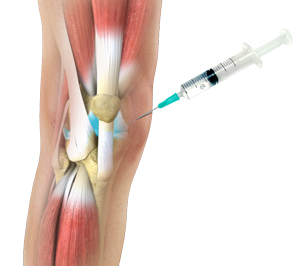

Russia’s healthcare infrastructure will continue witnessing a significant rise in several orthopaedic patients as several bone & joint-related disorders are likely to be caused by people’s eating & drink habits, their proactive lifestyles and the country’s harsh weather conditions. The rising occurrence of joint-related ailments such as knee osteoarthritis in Russia is a result of people performing physical labour in severely cold weather conditions. This has necessitated the adoption of viscosupplementation as an ideal medical procedure for injecting lubricating fluid in bone joints during surgeries. An in-depth analysis of the Global Russia Viscosupplementation Industry, conducted by Future Market Insights, projects that demand for three-injection viscosupplementation will gain traction over the next decade.